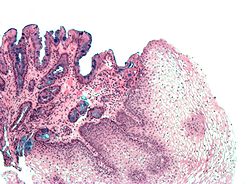

Metaplazija je vidljiva na endoskopiji ali se uzorak mora pregledati mikroskopski da se utvrdi koji je tip stanica dominantan. Kolonička metaplazija je karakterizirana peharastim stanicama epitela i preduvjet je za postavljanje dijagnoze Barrettovog jednjaka.

Mikroskopska slika Barrettovog jednjaka. Alcian blue stain.